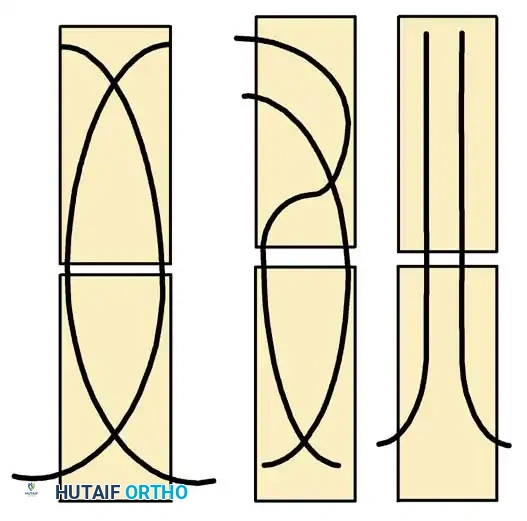

Biomechanics of ESIN:

ESIN relies on the principle of symmetric, three-point fixation. Two pre-bent elastic nails are inserted (usually retrograde from the distal femur) and advanced across the fracture site. The restorative forces of the bent elastic nails pushing against the inner cortical walls provide rotational and angular stability while allowing micromotion that stimulates robust secondary bone healing (callus formation).

Biomechanical principles of Elastic Stable Intramedullary Nailing (ESIN), demonstrating the three-point cortical contact required for stability.